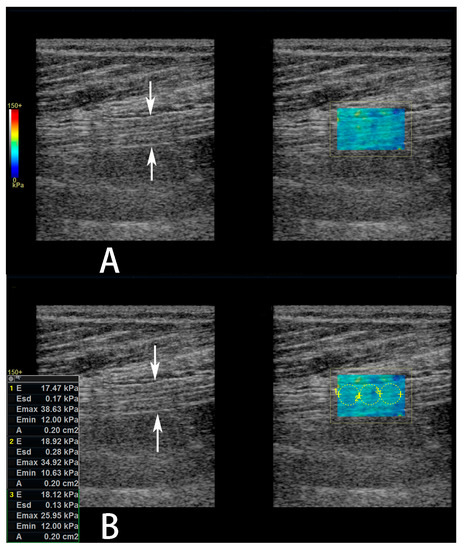

The sonographic parameters of the sciatic nerve were measured at about 3 cm proximal to the bifurcation of the tibial and common fibular nerves. Initially, transverse imaging of the bifurcation of the tibial and common fibular nerves were obtained, and the bifurcation positioned in the centre of the screen. Then, the transducer was rotated 900 to obtain longitudinal imaging of the nerve. Next, the transducer was moved towards the proximal thigh and the bifurcation disappeared on the screen. Lastly, the transducer was re-rotated 900 to obtain transverse imaging of the sciatic nerve. First, the CSA of the nerve was measured on the transverse image using a manual trace directly over the epineurium. Then, power Doppler US was performed in both transverse and longitudinal imaging planes (a parallel orientation to the sciatic nerve fibers) to observe the blood flow within the nerve. If the intraneural blood flow existed, then the spectral Doppler US was performed on the brightest vessels to observe the wave form and measure the velocity (for arteries, the peak systolic velocity (Vmax) and the minimal diastolic velocity (Vmin) were measured) and resistive index (for arteries, RI). The RI was defined as [1 − (Vmin ÷ Vmax)]. Last, SWE was performed in the longitudinal imaging plane. A color-coded box was superimposed on the image, and the size of the acquisition box was kept the same (20 × 14 mm) for all the patients. The spectrum scale of colors ranged from blue for softer tissues to red for stiffer tissues. When the frozen images of the nerves were obtained (probe was held stationary for 3 s), a circular region of interest (ROI) with a diameter of 2–4 mm was placed within the nerve according to the nerve’s diameter to represent the SWE stiffness value measurements. The mean elasticity within the ROI are expressed as the mean of three different measurements, and was reported in kiloPascals (kPa) (Figure 2).

Figure 2.

Measurement of sciatic nerve shear wave elastography (SWE) stiffness value. (A,B) Gray scale images (left panel) of the sciatic nerve and its affiliated color-coded SWE images (right panel) in a 61-year-old female diabetic patient with diabetic peripheral neuropathy (DPN). In the left panel, the sciatic nerve is shown between arrows. In the right panel, a color-coded box is superimposed on the image to indicate the sciatic nerve. (B) In the right panel, three non-overlapping circular regions of interest have been superimposed on the 2-D shear elasticity map that covered as much of the sciatic nerve as possible. The average SWE stiffness values within each region of interest (ROI) has been automatically calculated and shown on the screen.